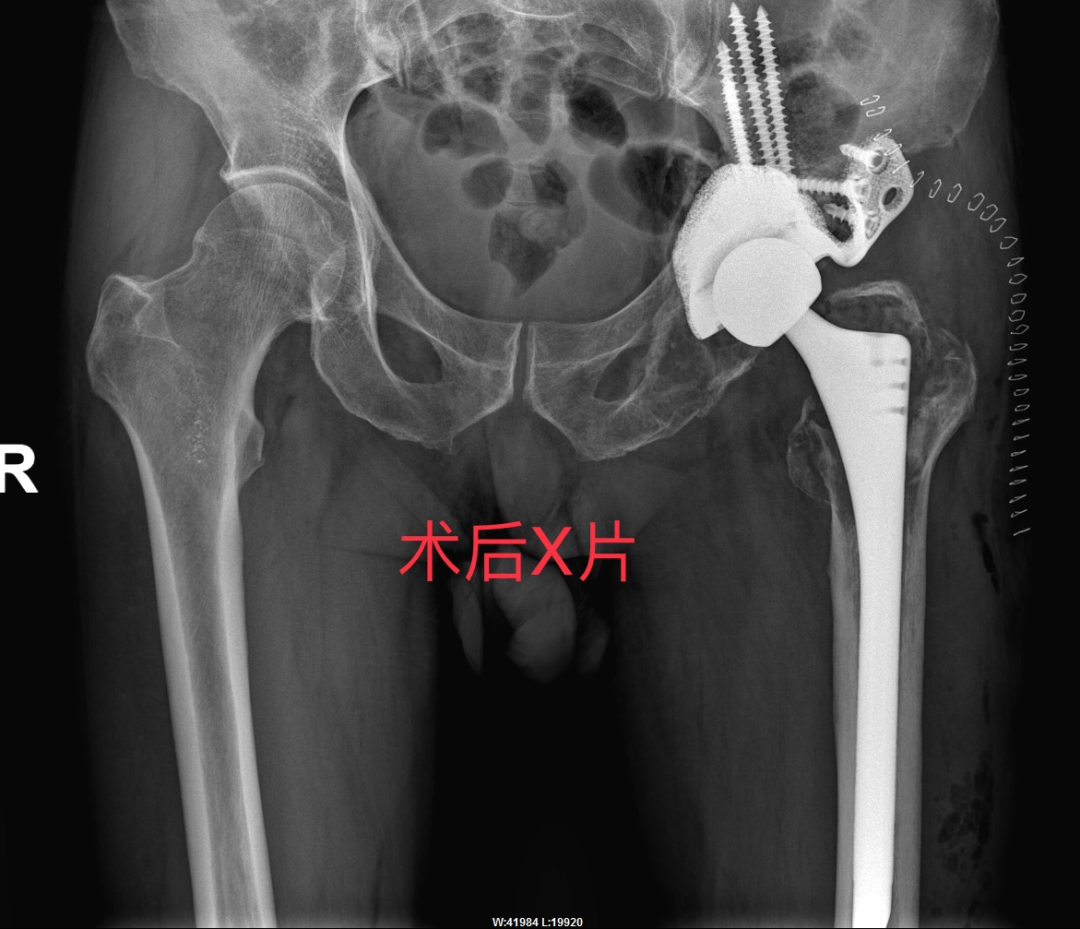

根据患者病情,考虑常规人工髋关节假体无法实现有效初始稳定性,而 3D 打印定制假体,能“量体裁衣” 般精准设计,突破常规手术局限,为曾爷爷量身打造独一无二的治疗方案,故选择3D打印个体化定制假体进行全髋关节翻修术。

我院骨伤中心与手术麻醉中心强强联合,组建 “硬核战队”,共同挑战这一全区首例的高难度手术。

此次手术的成功开展,不仅为患者重塑稳固关节,更以突破性技术填补区域医疗空白,为骨科手术进阶之路点亮新坐标。

麻醉苏醒后,曾爷爷的髋关节已能无痛自由屈伸;术后24小时内,借助助行器就能行走,生活起居已能完全自理!

通过X片、CT等评估骨缺损程度(如Paprosky分型),指导个性化方案设计。

2. 3D打印与定制化假体

根据患者骨骼形态打印假体,解决复杂骨缺损(如Paprosky IIIB型),实现“严丝合缝”的固定。